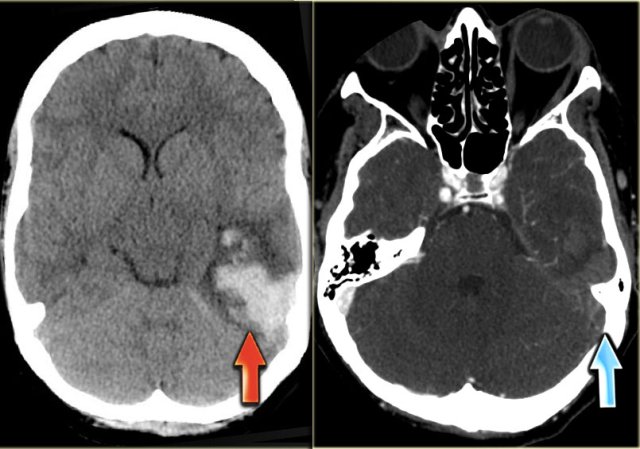

On the left images of a patient with hemorrhage in the temporal lobe.

When the hemorrhagic component of the infarction is large, it may look like any other intracerebral hematoma with surrounding vasogenic edema.

The clue to the diagnosis in this case is seen on the contrast enhanced image, which nicely demonstrates the filling defect in the sigmoid sinus (blue arrow).